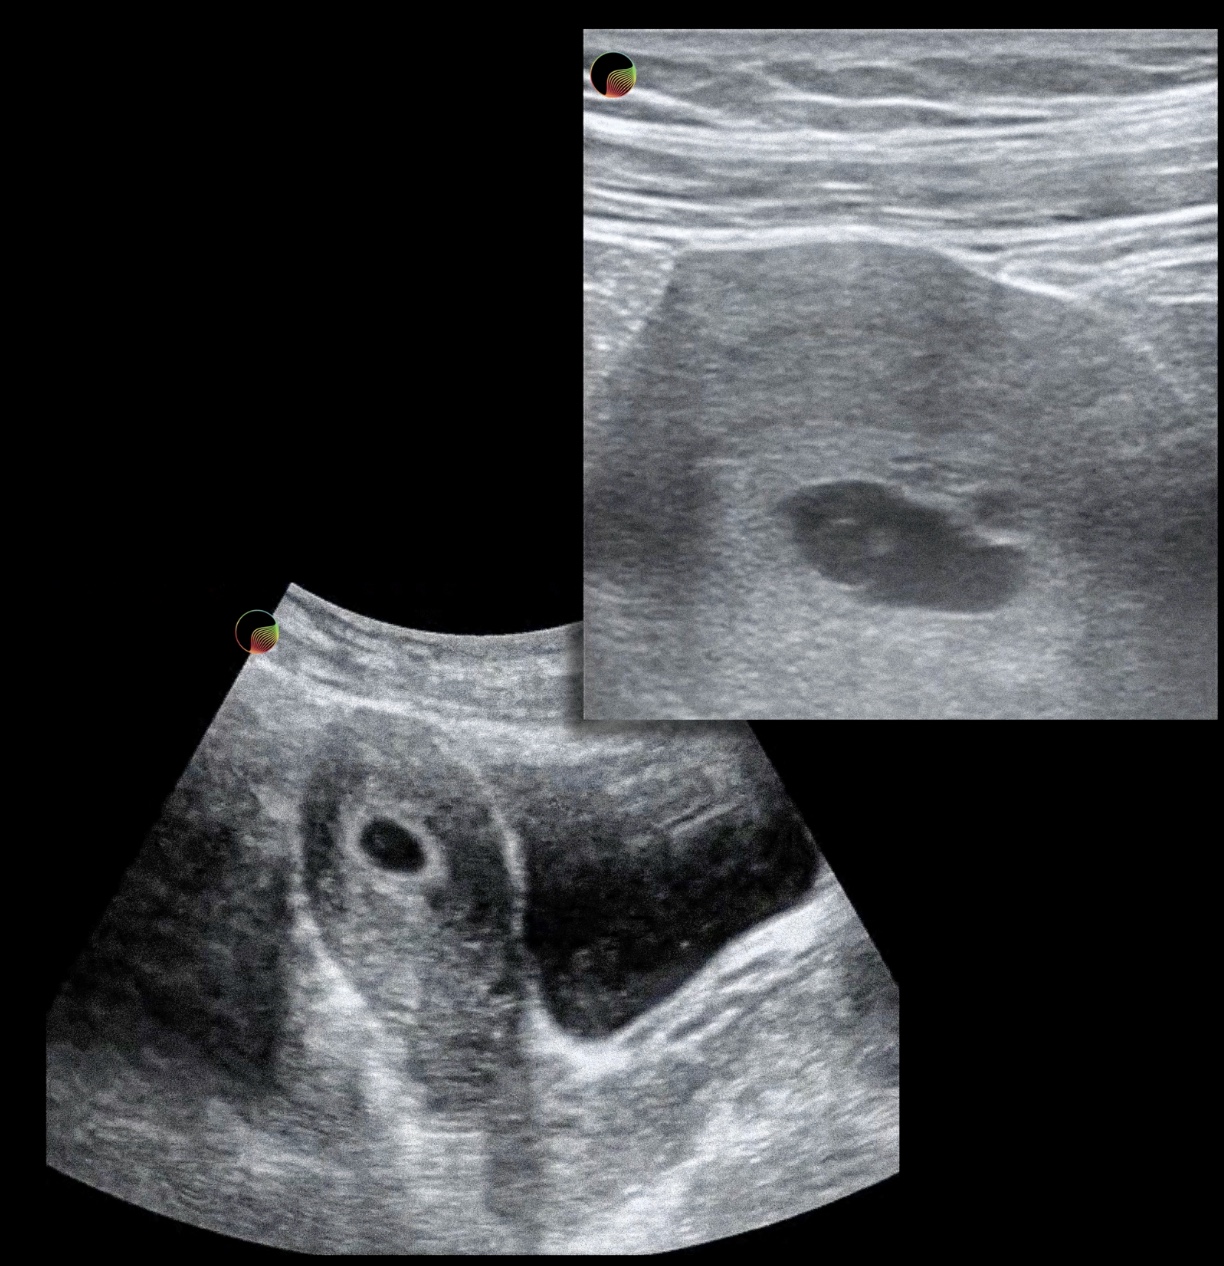

Check out our other lectures related to early pregnancy loss: - FemInEM Medication Primer: Mifepristone and Misoprostol - POCUS Basics: Intrauterine Pregnancy and Early Pregnancy Loss - FemInEM Core Content: Early Pregnancy Loss Explore more early pregnancy loss resources at https://feminem.org/resources/earlypregnancyloss